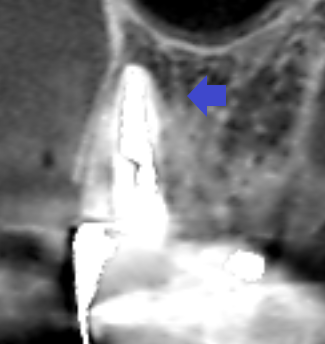

精密根管治療6カ月後の経過観察時の冠状断のCT画像です。矢印の先にあった膿の影が消え、歯槽骨が再生しています。

膿があっても必ずしも症状が出るとは限りません。また、場合によってはレントゲン画像などでも膿が映らないこともあります。本症例では、CT画像により膿の見落としをせずに膿の改善をすることができました。根管治療におけるCTスキャンの必要性が分かるケースでした。